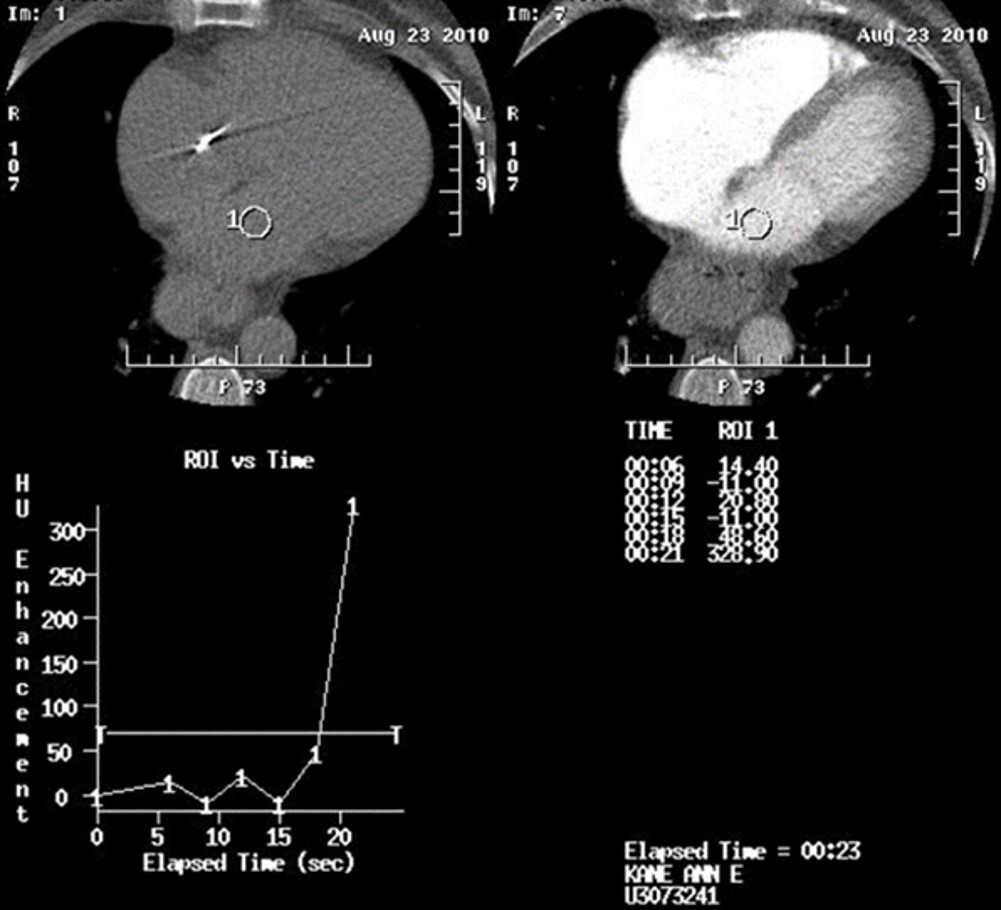

22

Q

If the inter scan delay is 2 secs, with a scan delay of 8 secs, based on the shown time-density curve generated by placing the ROI in the aortic arch, what is the total scan delay you would be required to set for a CTA to acquire images at peak contrast enhancement in the aortic arch?

23

In the shown time-density graph generated by the bolus tracking method, the attenuation threshold is set at approximately ? HU.